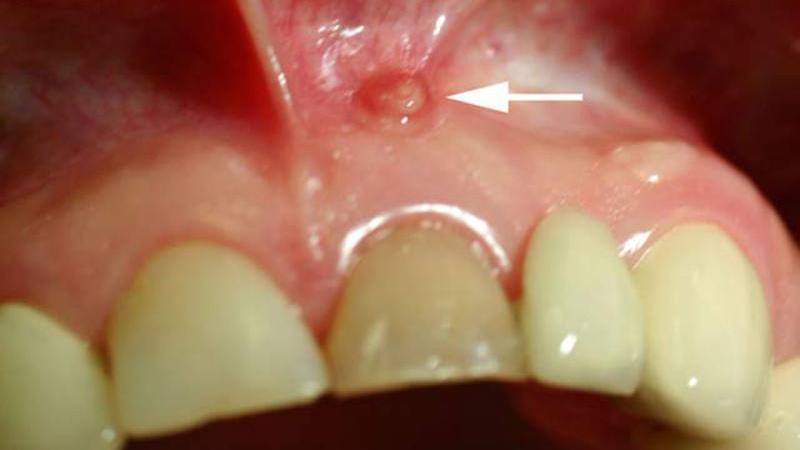

Киста в верхней и нижней челюсти является защитной реакцией организма на инфекции. Необходимо своевременно лечить различные заболевания, связанные с образованием жидкости, чтобы избежать угрозы для здоровья. Появление этого недуга может быть вызвано травмами зубов и десен, попаданием инфекций, зубными аномалиями развития, неправильным лечением зубных каналов и неправильно установленными протезными конструкциями, такими как коронки и протезы. Симптомы зависят от степени воспаления. Хроническая форма проявляется неприятными ощущениями в зубе, особенно при приеме твердой пищи, а также смещением зубов и потемнением. Увеличение кисты происходит, когда организм устает в борьбе с инфекциями, что приводит к развитию воспаления с гнойными скоплениями. В результате зуб начинает болеть, появляется сильная отечность и свищи. Пациенты также могут испытывать головные боли, слабость, общее недомогание, повышение температуры и увеличение лимфатических узлов. В таких случаях необходимо незамедлительно обратиться к специалистам.

Своевременное обнаружение проблемы является ключевым для наиболее эффективного лечения. Симптомы кисты верхней и нижней челюсти не имеют особых характеристик в ранних стадиях развития. Хотя челюстные образования могут быть врожденными, они также могут быть результатом периодонтита — воспалительного процесса тканей периодонта, вызванного неправильным лечением или отсрочкой обращения к стоматологу. Болезнь может проявляться в острой или хронической форме, последняя из которых может привести к развитию кисты. Периодонтит имеет три стадии: фиброзную, гранулирующую и гранулематозную. Фиброзная стадия относится к начальному развитию, характеризующемуся сужением щели периодонта. Гранулирующая форма определяется разрастанием кровеносных сосудов на верхушке корня, а дальнейшее прогрессирование приводит к гранулематозной стадии, где происходит разрушение тканей с образованием демаркационной линии. Эта линия разделяет разрушенные и здоровые ткани, что приводит к росту гранулемы. На нижней челюсти гранулема обычно располагается у многокорневых зубов, таких как первые моляры, а на верхней — в области премоляров и моляров.